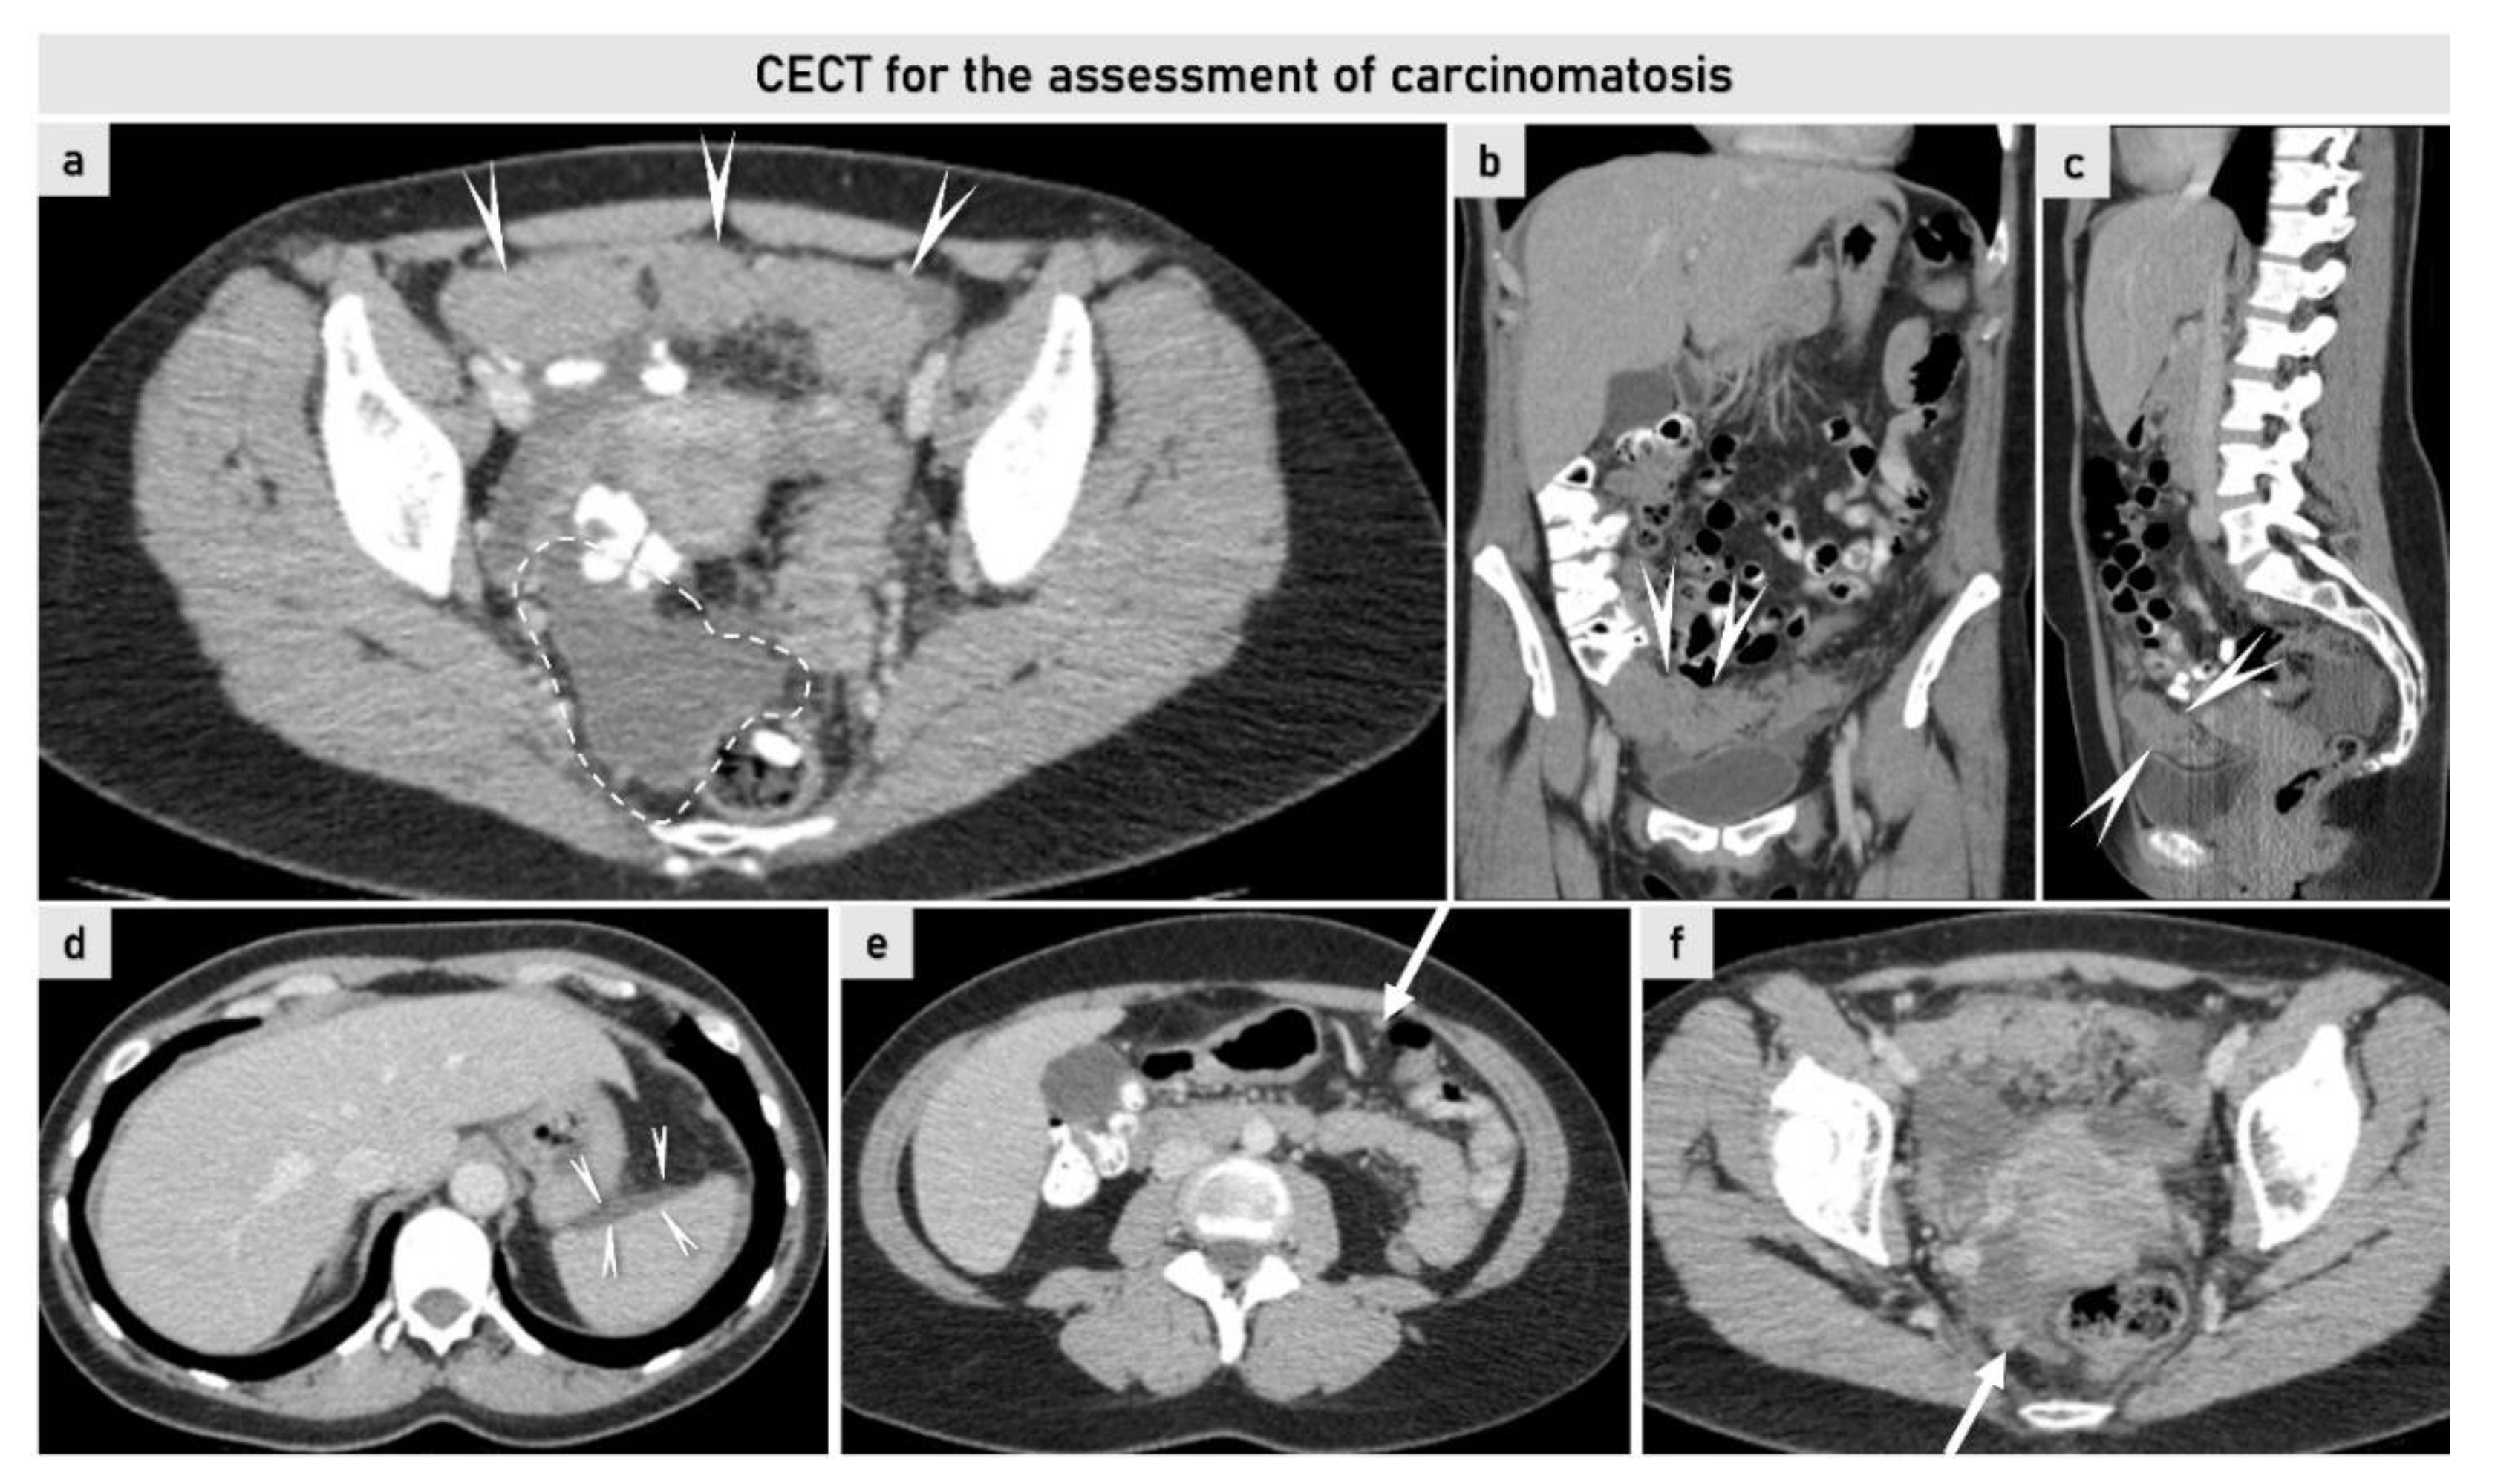

2.3.2. Computed Tomography

- Nougaret, S.; Addley, H.C.; Colombo, P.E.; Fujii, S.; Al Sharif, S.S.; Tirumani, S.H.; Jardon, K.; Sala, E.; Reinhold, C. Ovarian carcinomatosis: How the radiologist can help plan the surgical approach. Radiographics 2012, 32, 1775–1800; discussion 1800-3. [Google Scholar] [CrossRef]